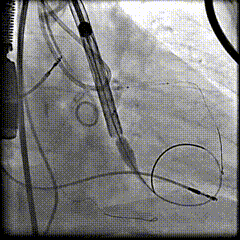

冠脉保护主动脉根部造影

18mm球囊预扩

过弓及跨瓣

瓣膜定位